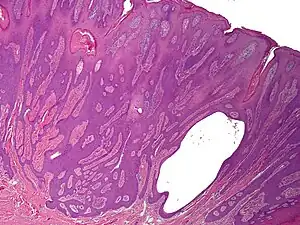

Syringofibroadenoma is a cutaneous condition characterized by a hyperkeratotic nodule or plaque involving the extremities.[1]

It is considered of eccrine origin.[2]